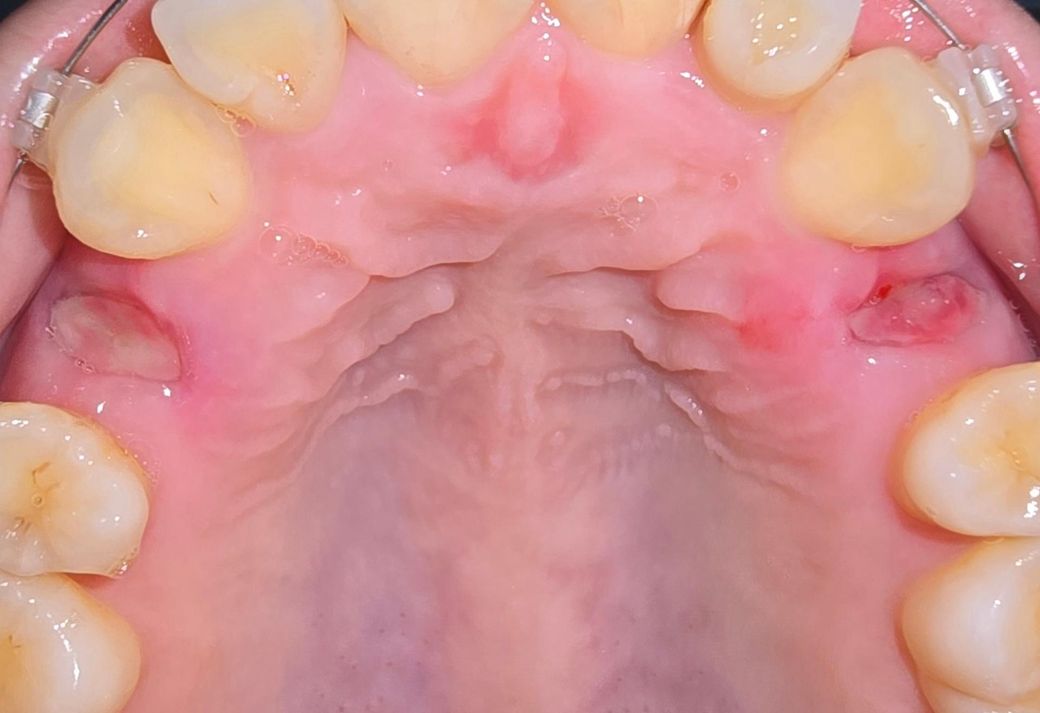

일주일 전에 교정으로 인해 상악 소구치 2개를 발치했는데요, 좌측은 하얀 조직이 생기며 잘 아무는 것 같은데 우측은 빨갛게 변하고 근처 잇몸 붓기가 있는 것 같아 혹시 염증이 생긴 건 아닌지 걱정됩니다. 둘다 잘 아물고 있는 것 맞을까요?

• 2번 째 사진

사진상 치아를 발치한 자리에는 염증은 없어보이며 앞니쪽엔 구내염이 있어보이기도 합니다.

사진으로 봤을 경우 잇몸은 잘 아물고 있는것으로 보입니다.

붉은색이 띠는것은 혈병이 형성되면서 보일수 있는것이기 때문에 걱정하지 않아도 될것으로 생각됩니다.

사진상으로 보면 발치를 한곳이 잘 아물고 잇는거 같습니다. 정상적인 반응이니 너무 걱정하지마세요.

약간 자극이 되어 발적이 있을 순 있으나 양쪽 다 치유 양호한 편입니다. 크게 걱정안하셔도 됩니다.